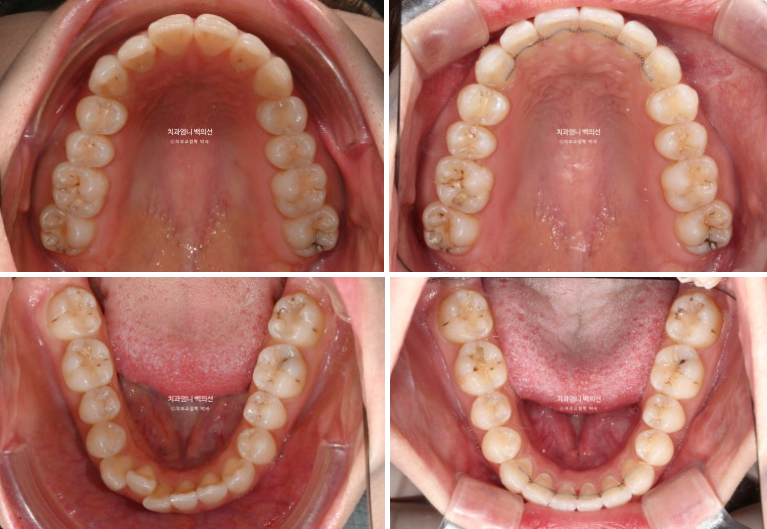

첫 세트 14개 장치를 모두 낀 후 모습입니다

중심선은 잘 맞고

원래 좋았던 어금니 교합은 잘 유지 되었고

배열도 좋습니다.

인비절라인라이트 재제작 기회가 1번 있지만 경과가 좋아 재제작 없이 마무리 했습니다.

중심선은 잘 맞고 과개교합도 좋아졌고 잇몸라인의 개선도 보입니다.

솟아있던 아래 앞니 덧니를 합입시켜 주변치아와 높이를 맞추었고 그 과정에서 잇몸라인도 자연스럽게 높낮이가 개선이 됩니다.

총 치료기간은 5개월 입니다.

치근흡수는 없으며 치근평행도는 좋습니다.